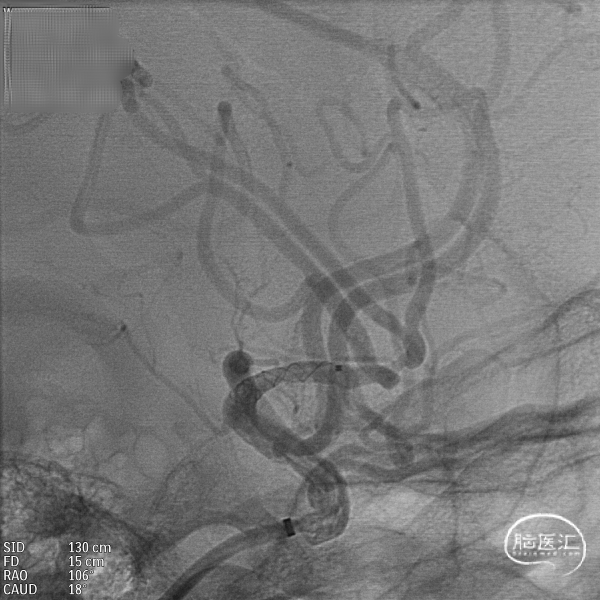

DSA:DSA提示右侧大脑中动脉M1段动脉瘤,左侧大脑前动脉A1段发育不良。

其他血管造影未见明显异常。

术前诊断:动脉瘤位于M1主干,考虑夹层动脉瘤可能大。

载瘤动脉远端血管直径:2.4mm

载瘤动脉近端血管直径:2.5mm

动脉瘤尺寸:(瘤颈口宽度2.0mm/瘤体高度1.86mm/瘤囊宽度1.85mm)

手术方案:血流导向装置植入术。

微导管到位:Synchro微导丝引领支架微导管通过病变血管进入大脑中动脉M2段。

支架到位,原位释放,前段打开。

造影确认支架远端打开充分,贴壁良好,继续推送支架。

术后造影:支架充分覆盖动脉瘤瘤颈,贴壁良好,瘤体内可见造影剂滞留。

术后支架显影:定位精准,未覆盖颞前动脉及大脑前动脉。